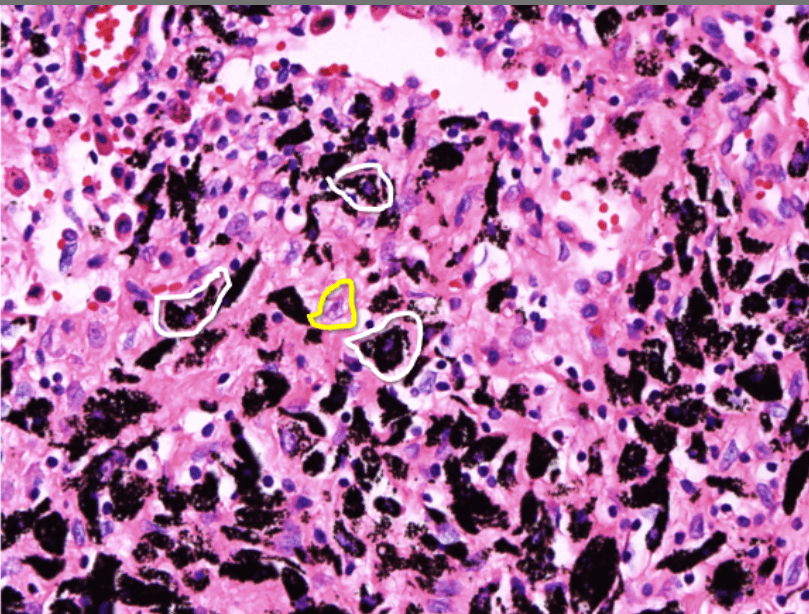

Pathology Micro-2

Tumor Description:

1. border(infiltrative到哪裡/circumscribed/capsule)

2. architecture

3. cell 長相

4. stroma

5. 其他周邊異常

(melanin pigment)